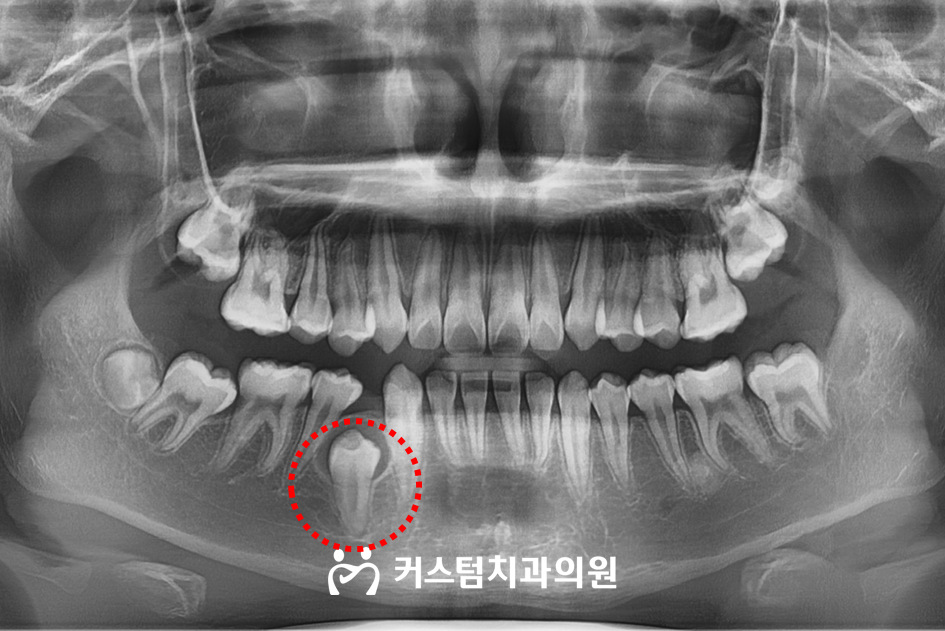

진단 과정에서 촬영한 엑스레이 사진을 살펴보니, 하악 오른쪽의 영구치 하나가 잇몸 밑 치조골 속에 묻혀 있는 매복 상태라는 사실을 확인할 수 있었는데요.

문제는 이 매복치로 인해 전체적인 치열이 한쪽으로 쏠리면서 중심선이 틀어지고, 좌우의 교합 균형도 무너졌다는 점이었습니다.

더 나아가, 치열이 비뚤어짐에 따라 송곳니와 측절치 사이에는 공간이 발생하고 상하교합도 엉성해진 상태였습니다.

대구치도 정상적인 위치에서 벗어나 맹출 경로가 좁아진 상태였죠. 이러한 문제들은 단순히 치아 배열만의 문제가 아니라, 전체적인 얼굴 윤곽과 기능에도 영향을 미칠 수 있는 상황이었습니다.